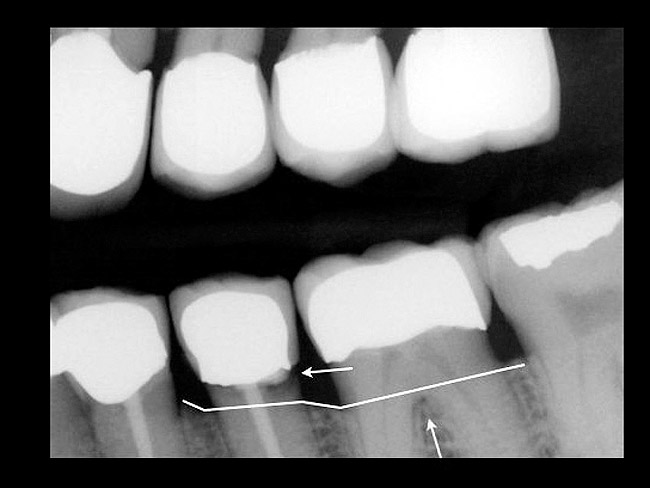

Figure 2  EVALUATION PARAMETERS  The location of the fracture relative to the alveolar crest makes this tooth a more challenging decision on whether to restore or extract.

Figure 2